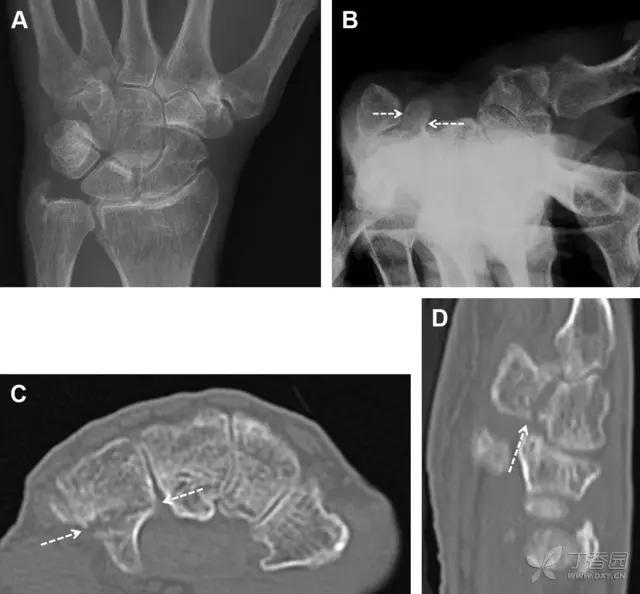

31 舟状骨骨折

舟状骨骨折 60%~70% 发生于腰部,15% 发生于近极, 10% 发生于远极, 8% 发生于远端关节面。除了常规的前后位、侧位、斜位片外,还需要拍专门的舟状骨位片(腕关节尺偏,以舟状骨为中心的腕关节前后位片),特别是鼻烟壶有压痛时。

图 2 舟状骨骨折 (A、B)第 1 例患者,舟状骨远极关节内骨折(白色箭头),斜位片显示较清楚(B);(C、D)第 2 例患者,舟状骨腰部骨折(虚线箭头),斜位片显示较清楚(D);(E~H)第 3 例患者,舟状骨近极骨折,常规 X 线片均未看到骨折,而在舟状骨位片上才能见到骨折(虚线圆)